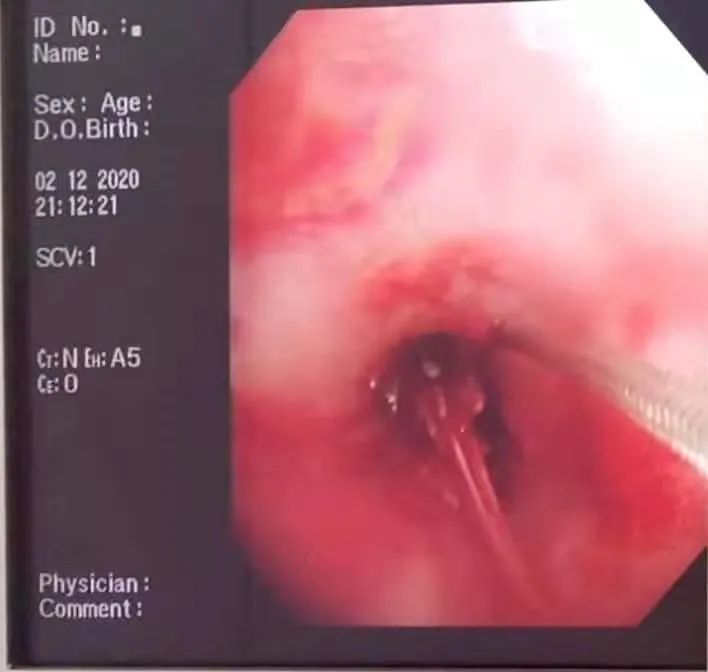

片刻,严主任已赶到并准备就位。只见镜头进入左总支气管,一只河虾的额刺赫然在目,完全阻塞了气管腔。所幸,额刺并没有扎入气管道引起大出血,不然后果不堪设想。

“准备异物钳。”严主任指示道。

“异物钳准备!”周燕回应。

“开!”、“夹!”随着严主任一声令下,一只完整的虾头被取了出来……

“得再下去看看,气管里可能还有东西没取出来!”严医生说道。